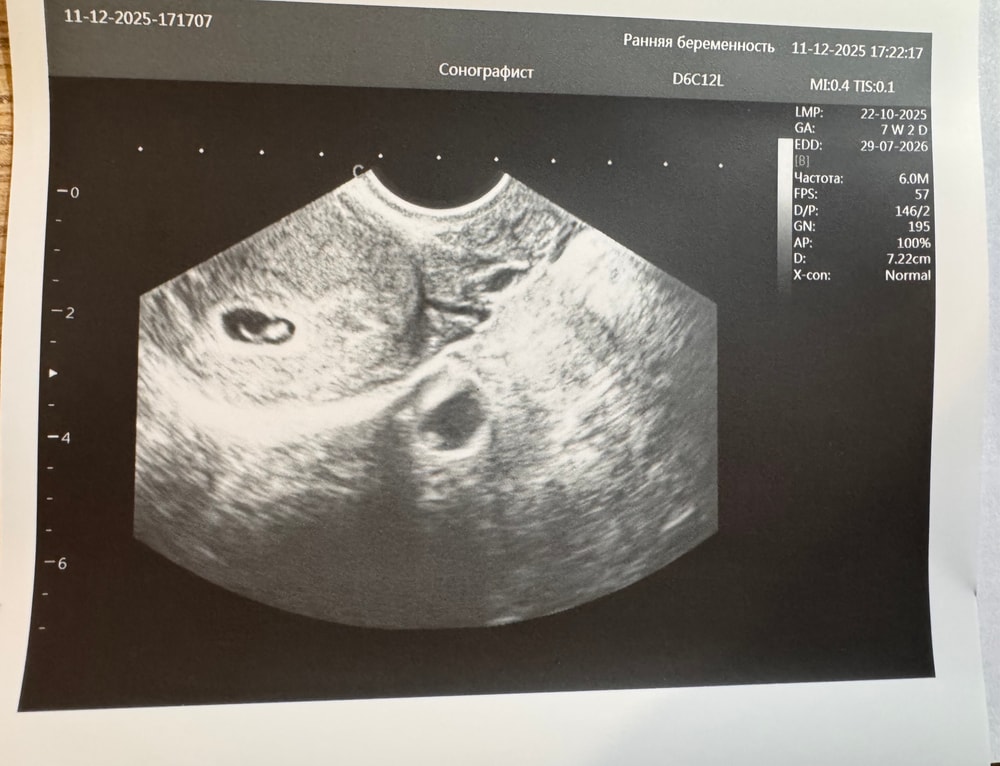

Результаты УЗИ

была сегодня на узи 34дпп, уже готова была услышать, что все…

и о чудо, мне показали сердечко моего эмбриончика🥰сказали надежда еще есть!

Ре добавила клексан на 4-5 дней и потом на узи.